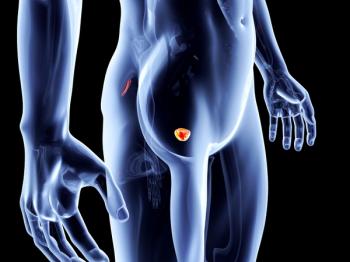

Patients with PSMA-positive metastatic castration-resistant prostate cancer can now be treated with Pluvicto, which may provide hope to an unmet need in this patient population.

Patients treated with Lutetium-177 PSMA-617 tended to experience improvements in quality of life related to the aches and pains that can come from bone metastases.